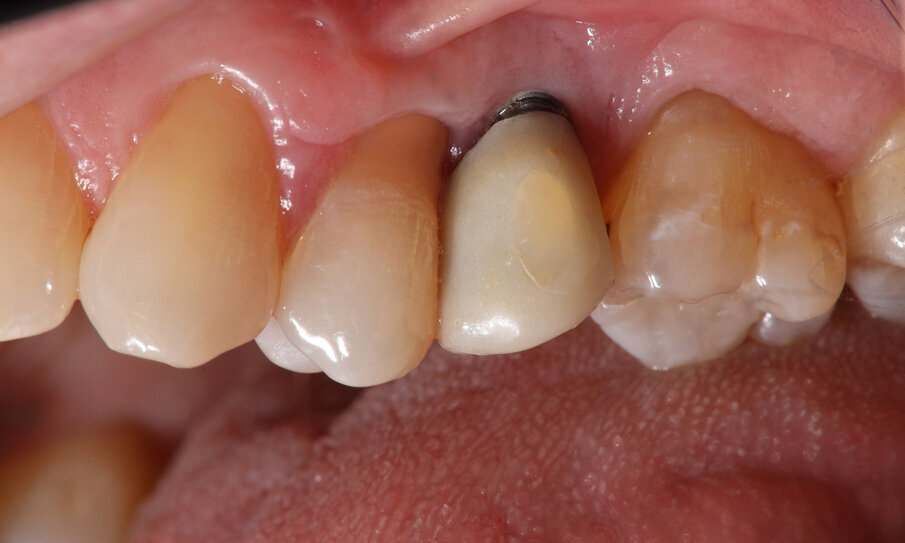

Quinta e sesta seduta A 90 gg si effettua seduta di richiamo con deplaquing, privilegiando l’impiego di polvere di glicina con sistema air polishing (CombiTouch Mectron Spa) con multidirezionalità del getto prima in senso apico-coronale, poi in direzione corono marginale e infine perpendicolare alla superficie implantare esposta, con l’obiettivo di decontaminarla al meglio, senza ledere i tessuti circostanti. A 6 mesi dal baseline (t4) si esegue la rivalutazione. Vengono eseguite fotografia e rx endorale del sito di controllo (Figg. 5, 6). All’esame visivo e palpativo i tessuti molli perimplantari si presentano in buono stato, in termini di colore e consistenza. All’esame radiografico si apprezza una remineralizzazione dell’osso. Viene eseguita la terapia professionale mediante la medesima tecnica di air polishing con polveri a bassa granulometria, al fine di disgregare l’eventuale biofilm patogeno, potenziale causa di recidiva. In entrambe le sedute viene eseguito un rinforzo motivazionale.

Fig. 5

È possibile apprezzare radiograficamente un’aumentata mineralizzazione ossea, con un ulteriore miglioramento rispetto alla prima rivalutazione post-terapia. Questo dato indica la risoluzione dello stato infiammatorio cronico e conferma il buon potenziale rigenerativo della terapia adottata. Contestualmente, all’esame visivo dei tessuti, si osserva un riposizionamento in direzione coronale del tessuto molle, con un aumento dei volumi gengivali rispetto al tempo t4, anch’esso indicativo del potenziale rigenerativo stimolato dalla strategia terapeutica a livello del tessuto connettivo gengivale.